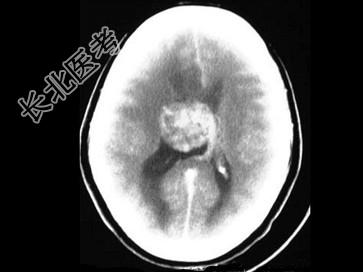

- 单项选择题女,31岁, 癫痫发作,头痛, 头晕,结合图像, 最可能的诊断是 ( )

A、脑膜瘤

B、脑囊肿

C、星形细胞瘤

D、脑膜炎

E、室管膜瘤